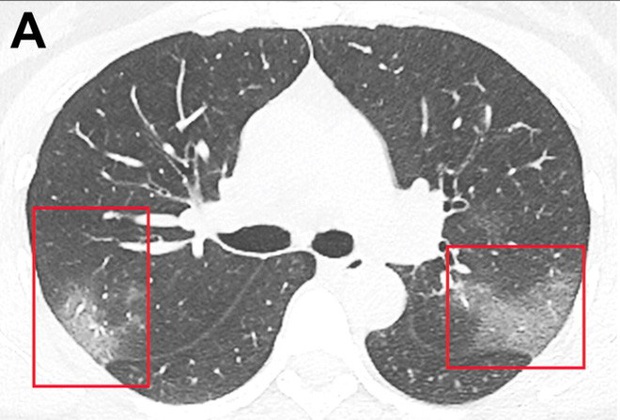

Ảnh chụp cắt lớp CT một lá phổi của bệnh nhân Covid-19 mô tả các thương tổn ở hai thùy.

Trong thời đoạn thứ ba, tổn thương phổi đấu tiến triển có thể dẫn đến suy hô hấp. Quy mô của cuộc tấn công lớn đến nỗi ngay cả khi bệnh nhân may mắn sống sót, các thương tổn này ở phổi cũng sẽ trở thành những vết sẹo vĩnh viễn.

Giống như SARS trước đây, Covid-19 có thể đục ruỗng phổi, để lại một lá phổi thủng lổ đổ giống như tổ ong. Các tổn thương này có thể được nhìn thấy trên phim chụp X-quang của bệnh nhân, hai lá phổi đơn giản là trắng xóa.